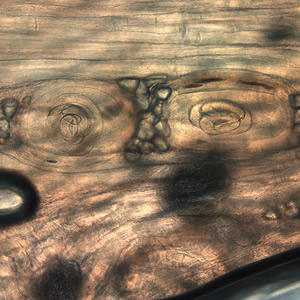

Case #199 – March, 2007

A huntsman killed a bear and prepared it for eating and freezing by cutting it into roasts, steaks, and grinding the trimmings. Later that same day, he ate a burger made from some of the fresh meat and cooked rare. Approximately two and a half to three weeks later, the hunter experienced fever, diarrhea, and muscle pain. However, medical attention was not sought for another six weeks. He had elevated eosinophilia and several laboratory tests were ordered. The Division of Parasitic Diseases’ reference diagnostic laboratory received some of the bear meat for examination. A digestion technique using 0.1% pepsin and 0.1% hydrochloric acid was used on the meat and a muscle squash was made from the softened tissue. Figure A, taken at 400× magnification, and Figures B-E, taken at 1000× magnification, show what was observed. What is your identification of the objects in the meat? What is your diagnosis? Based on what criteria?

Figure A